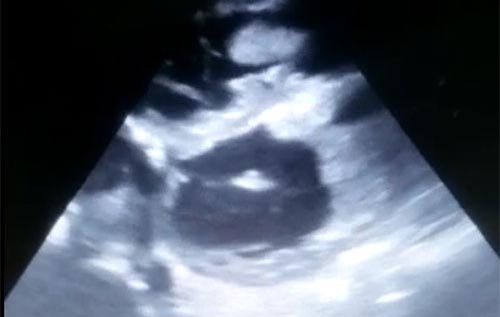

Semana 11

Paciente 73 anos com IC descompensada de longa data.